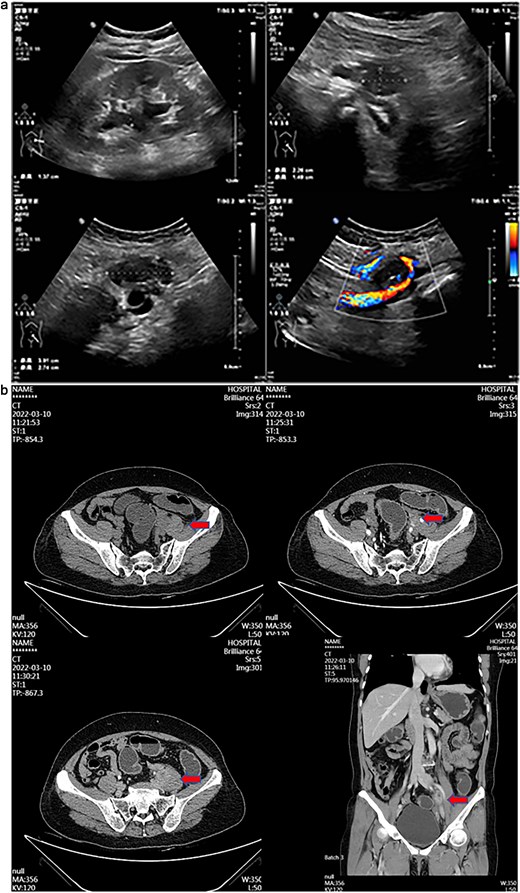

A 55-year-old female patient has experienced persistent pain in her left lower back for more than 3 weeks. Ultrasound examination revealed a hypoechoic mass and a mixed echoic mass beside the left iliac vessel, the nature of which was undetermined. There was a small amount of effusion in the left kidney. It was considered possible that the middle section of the left ureter was compressed (Fig. 1a). Computed tomography (CT) examination showed a nodular soft tissue density shadow was observed beside the left iliac vessel, ~17 × 20 × 30 mm in size. After enhancement, it showed annular enhancement. The lesion was slightly compressed adjacent to the left ureter, and above this level, the left ureter and the left renal pelvis and calyces were slightly dilated. This suggests that a nodular soft tissue density shadow beside the left iliac vessel is of undetermined nature, and the possibility of metastasis is high (Fig. 1b).

(a) Transabdominal ultrasound image showing hypoechoic and mixed-echoic masses adjacent to left iliac vessels with associated mild left Hydronephrosis and mid-ureteral compression. (b) Contrast-enhanced CT image demonstrating ring-enhancing left adnexal mass and left iliac vessel nodule with associated ureteral compression and mild hydroureteronephrosis.